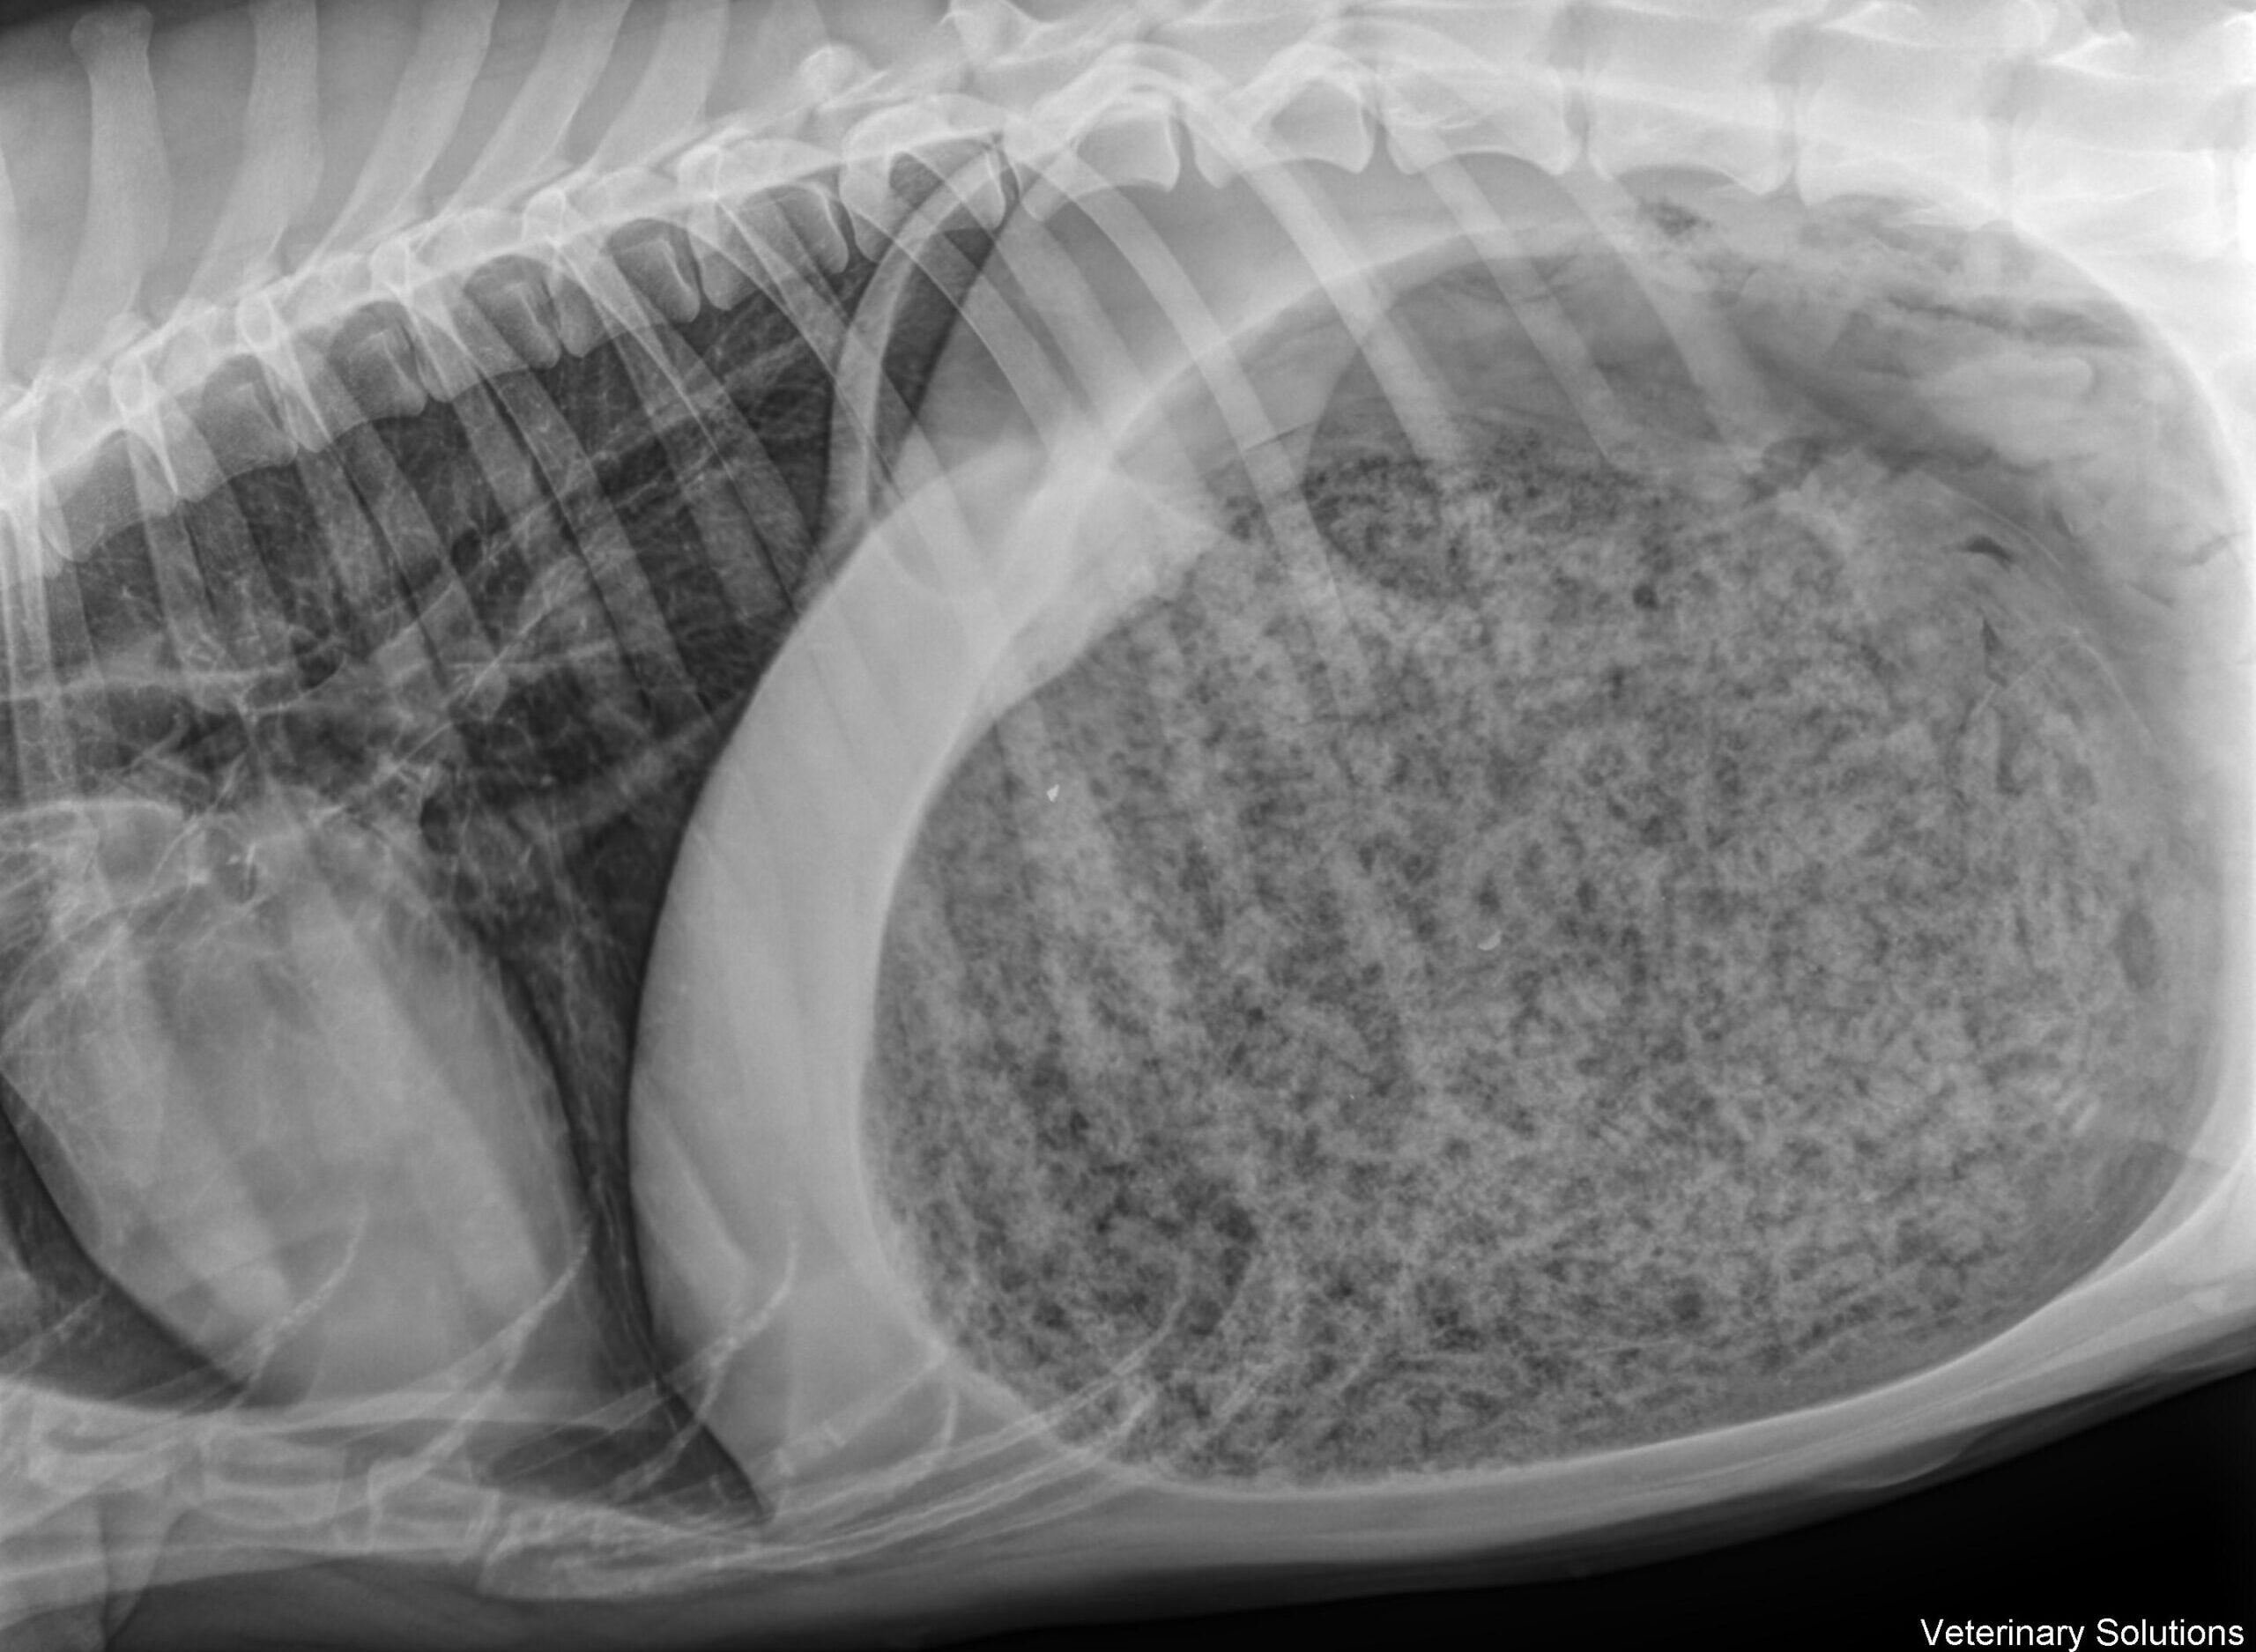

Le Syndrome de Dilatation-Torsion d’Estomac (ou SDTE)